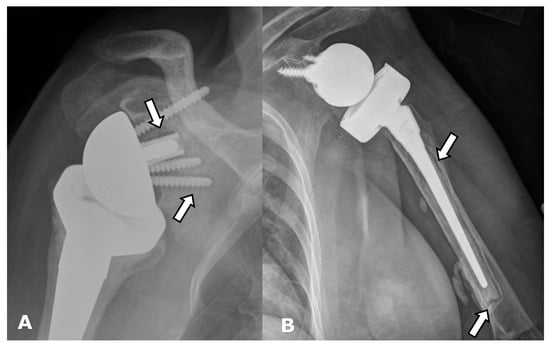

4.2.2. Stress Shielding and Fractures

5.3. Revision Shoulder Arthroplasty